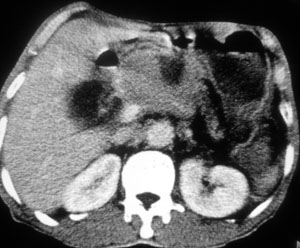

以下是引用liaoqiang在2008-6-13 15:20:00的发言:[br]1胰头区域肿块,胰管和胆管轻度扩张。肿块包绕肠系膜上静脉。考虑胰头癌可能性大。2胃底部壁增厚。

以下是引用liaizhi在2008-6-13 16:15:00的发言:[br]考虑胰头癌可能性大(胰头增大,胆囊增大,胰尾部及胆总管扩张.)胃大弯部胃壁增厚.胃占位?